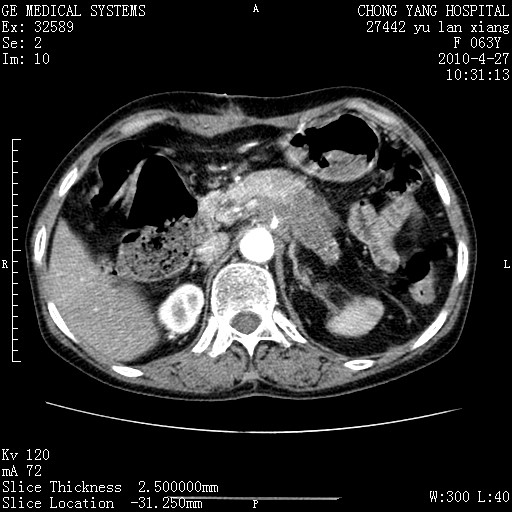

标题: CT26066:F63Y 上腹正中压痛半月,CA199:7400u/ml,MR示胰腺炎伴 [打印本页]

标题: CT26066:F63Y 上腹正中压痛半月,CA199:7400u/ml,MR示胰腺炎伴

胰腺癌侵犯腹腔动脉干-分支、胃壁、左侧膈肌伴胰周及腹膜后淋巴结转移、胆囊切除术后。

胰腺癌侵犯腹腔动脉干-分支、胃壁、左侧膈肌伴胰周及腹膜后淋巴结转移、胆囊未显影。